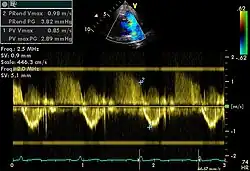

Doppler

Spectral doppler

Spectral doppler is presented similarly to M-mode in which the doppler information is plotted as a spectrogram. This can be both "continuous" and "pulse" wave where the former shows the spectrum along a specific line and the latter shows within a small window along that line. Continuous wave is better at showing maximal velocities and pulse wave is better for showing flow through a small volume.

Spectral doppler is often used for quantification of flow. For example, the aortic valve area can be estimated using the continuity equation by measuring the velocity time integral (VTI) of the aortic valve & LV outflow tract; the VTI is calculated by tracing the flow on the spectral doppler curve. Spectral doppler is also useful for calculating the maximum flow and mean flow through a valve (used to grade valve stenosis).